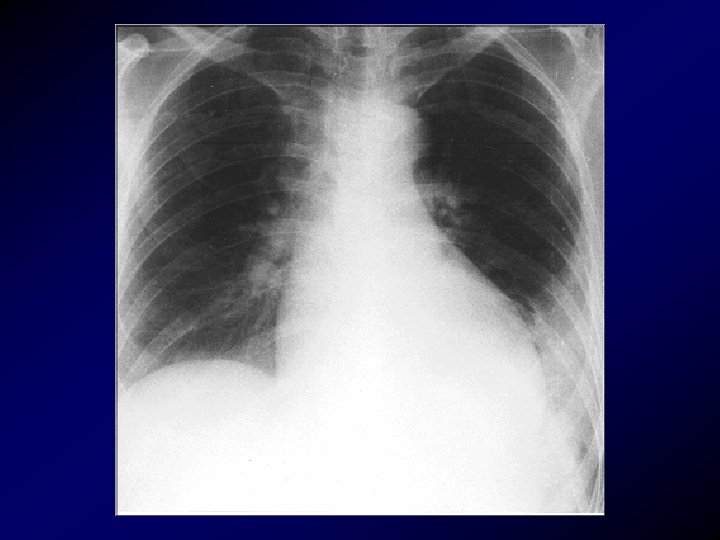

Radiografia del torace • può escludere la presenza di altre patologie: pneumotorace, polmonite, edema polmonare acuto, atelettasia. • Nell' embolia polmonare può essere normale; solo in alcuni casi senza infarto polmonare può fornire elementi utili: improvvisa interruzione dell' ombra di un ramo arterioso con iperdiafania della relativa zona polmonare, dilatazione del tronco dell' arteria polmonare e del ventricolo destro con possibile ingrossamento ilare, atelettasia basale a piastra. In caso d'infarto polmonare non prima di 24 -36 ore dal fatto acuto può mostrare opacità rotondeggianti, lineari, di rado tipicamente triangolari, localizzate più frequentemente nei lobi inferiori soprattutto a destra. Talora le opacità si accompagnano ad un versamento pleurico che può mascherare l'infarto (più frequente a destra) o l'innalzamento dell' emidiaframma omolaterale.